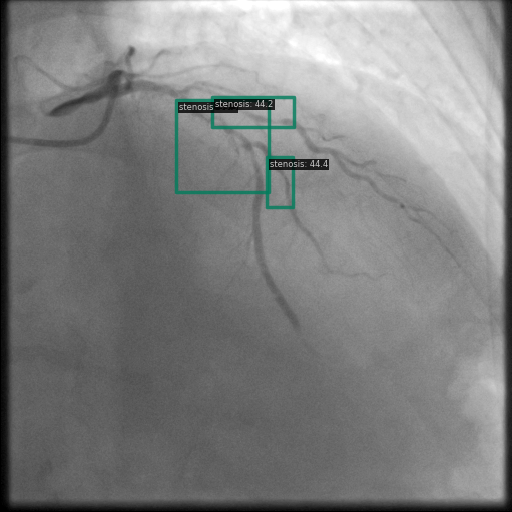

Figure 1 shows sample images from the ARCADE dataset with annotations for stenosis detection. The annotations highlight regions of arterial narrowing, providing ground truth data for training and evaluating object detection models.

To further assess the detection performance, qualitative results for three test images are presented in Figure 2. The first column shows the original images with ground truth annotations. The second, third, and fourth columns depict detections from DINO-DETR, Grounding DINO, and YOLO, respectively.

(a) Original (b) DINO-DETR (c) Grounding DINO (d) YOLO

The qualitative comparison in Figure 2 reinforces the trends observed in the quantitative evaluation. DINO-DETR produced fewer detections, occasionally missing relevant stenotic regions, consistent with its conservative detection strategy aimed at minimizing false positives [6]. Grounding DINO, although capable of identifying more regions, sometimes resulted in cluttered predictions due to over-detections [7]. YOLO provided a reasonable trade-off by effectively capturing anatomical structures while maintaining relatively high confidence scores and clear visualizations [5].